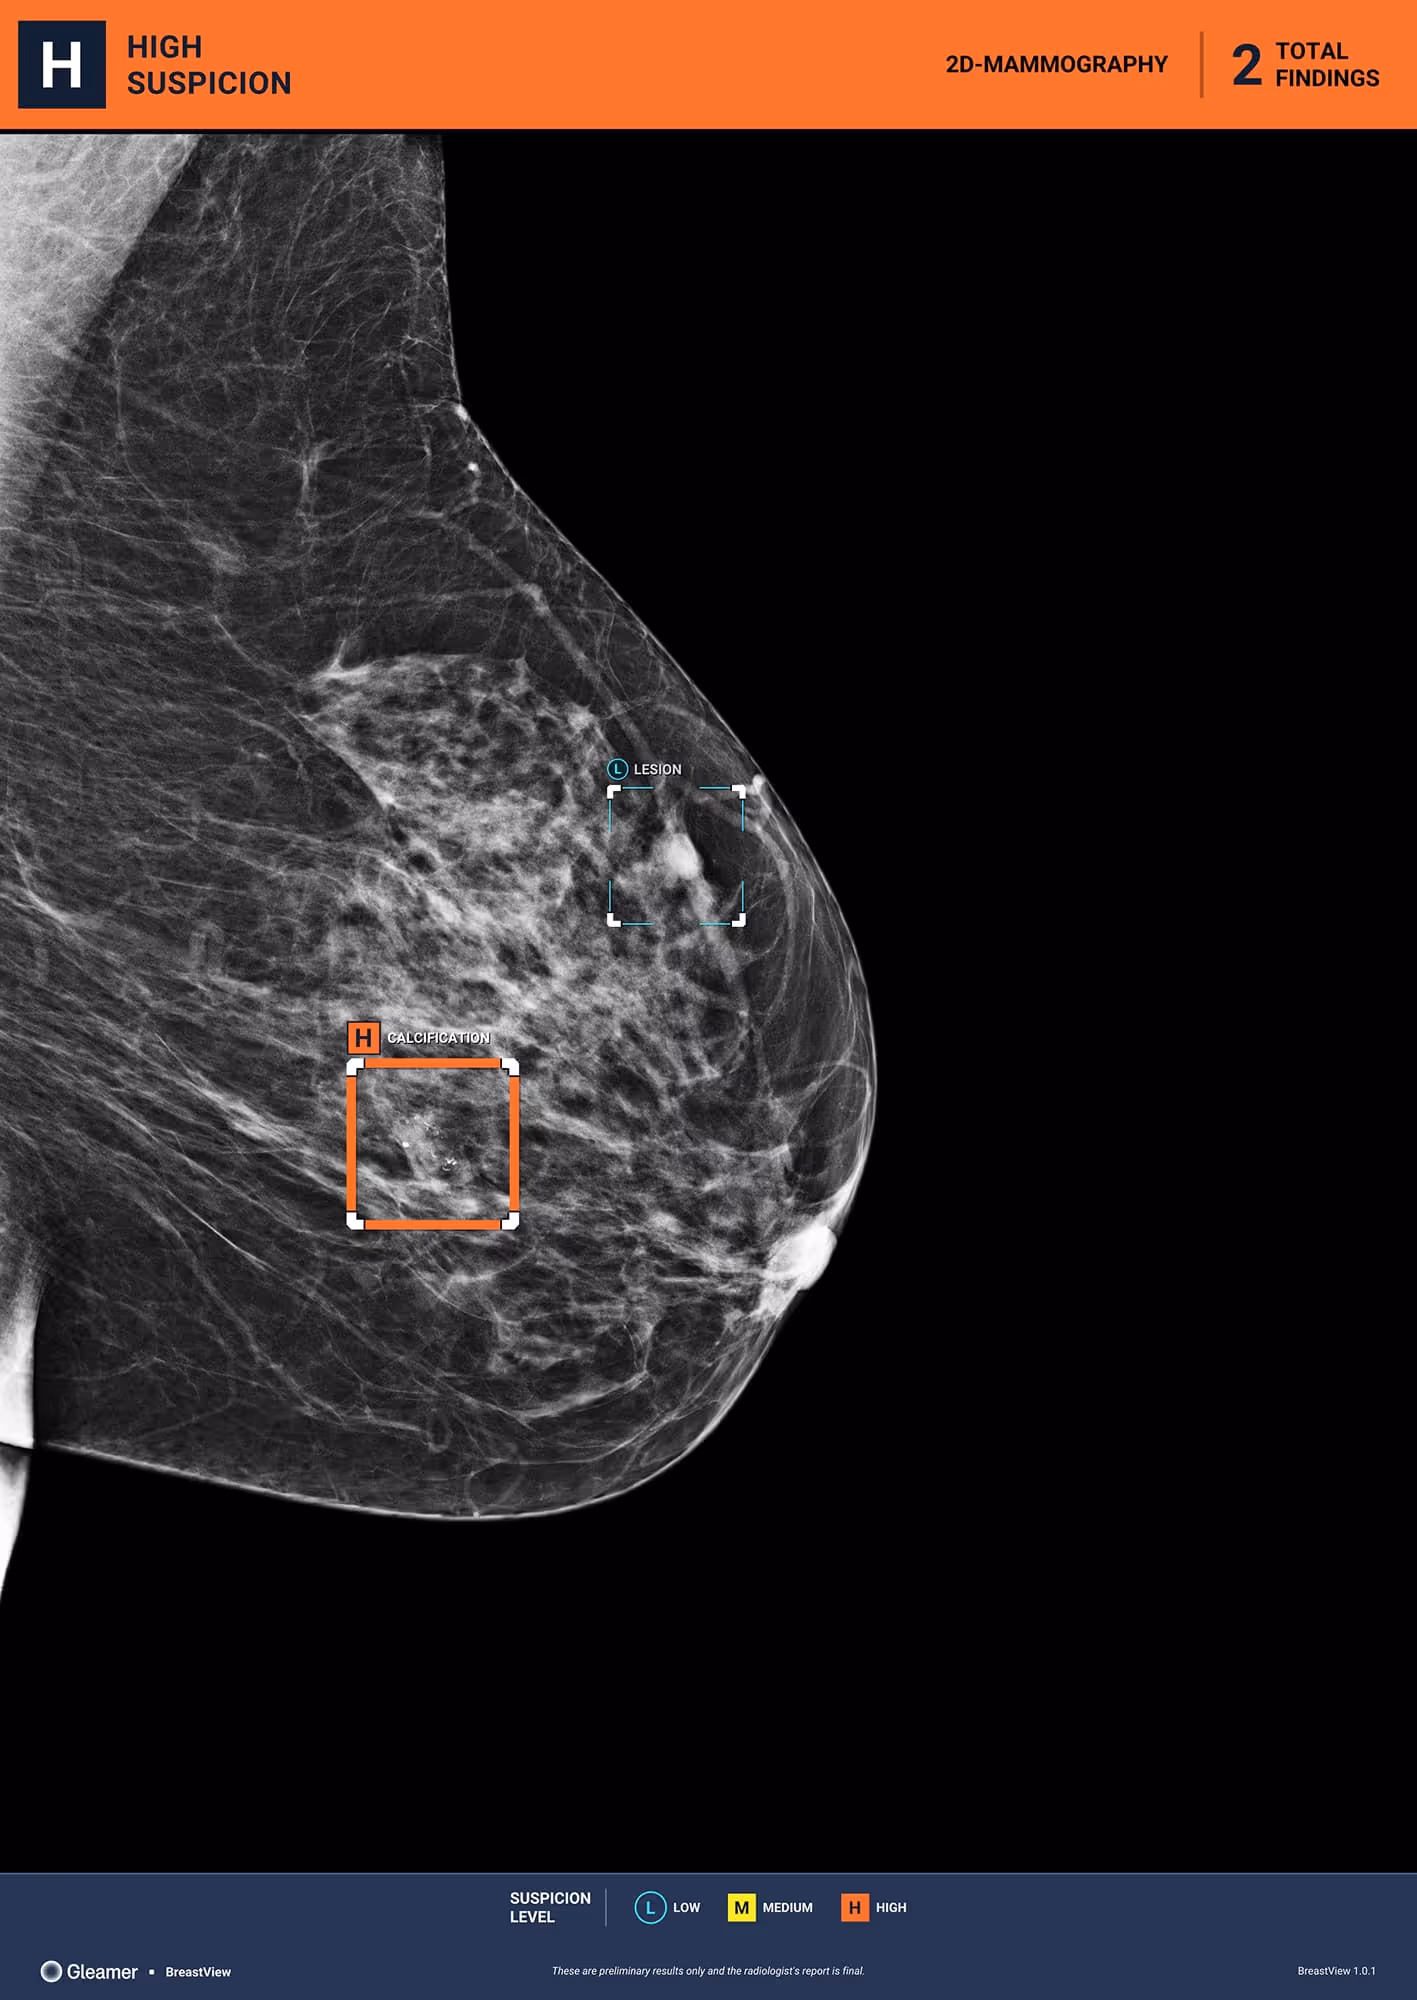

Indication

56 y.o patient presenting as part of organized screening.

Results

BreastView detected a benign cyst and micro-calcifications that were a ductal carcinoma in situ (DCIS).